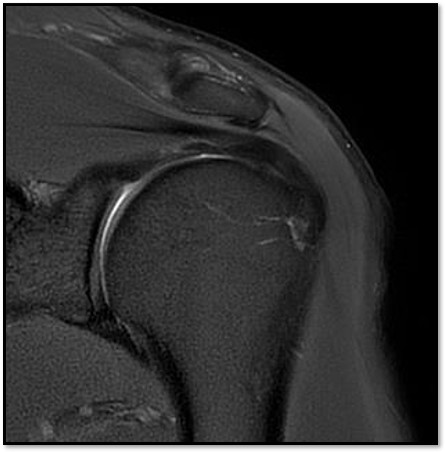

MRI를 검토해보았습니다. 확실히 회전근개 극상건에 부분파열이 있었습니다.

케이스 1: 관절면측 파열 → 축소봉합술

환자: 45세 남성, 테니스 동호회

진단:

MRI: 극상건 관절면측 부분파열 (약 40%)

파열 양상: 가로 파열, 깔끔함

치료:

축소봉합술 (특수 드릴 + 콜라겐 봉합사)

재생주사 병행

재활 운동

결과:

12주 후 초음파: 봉합 부위 안정적 유지

6개월 후 테니스 복귀